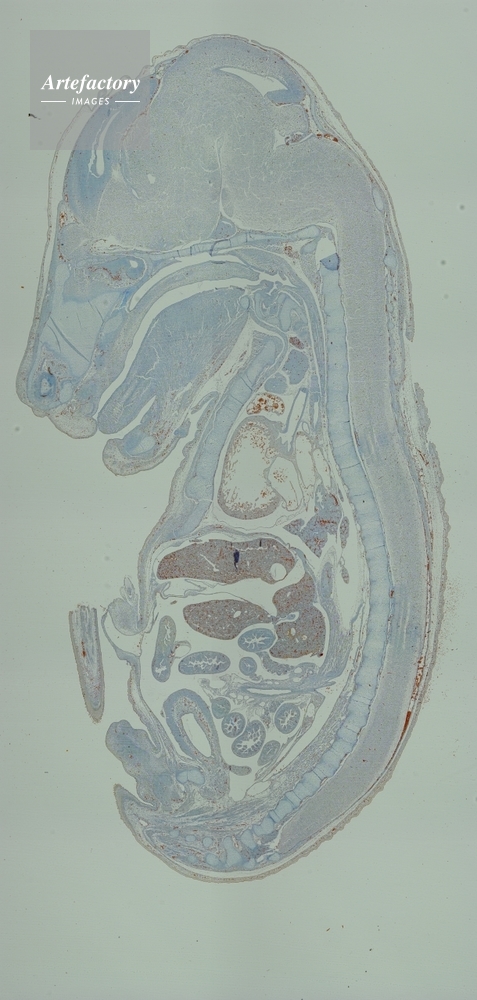

| 作品番号 | 03400318 | クレジット表記 | (c)OLYMPUS CORPORATION Technolab / Artefactory | |

| 作品タイトル | 不明 | モデルリリース | なし | |

| 作家 | OLYMPUS CORPORATION Technolab | プロパティリリース | なし | |

| キャプション | 合成画像 | 制限事項 | ||

| ソース | ピクセル数 | 610px × 1280px | ||

| 撮影年月日 | 2007/7/2 | データサイズ | ||